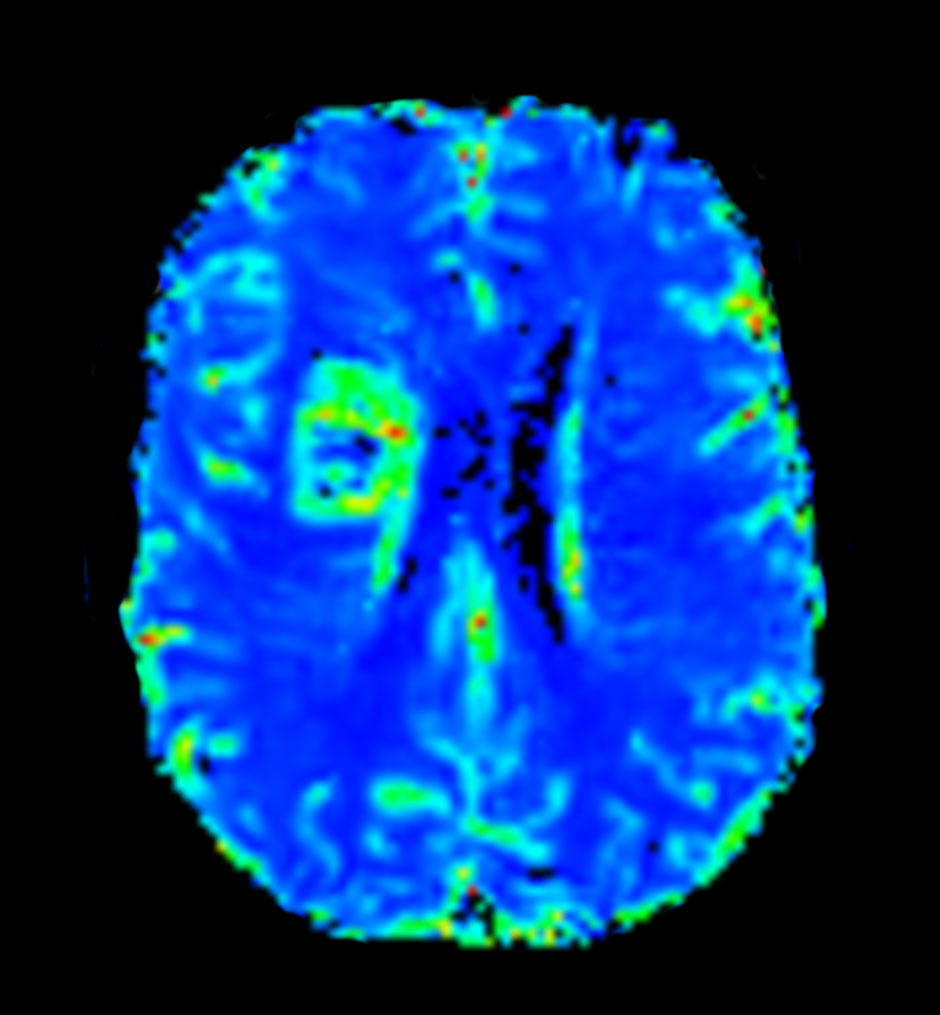

Axial T2* Perfusion (Index)